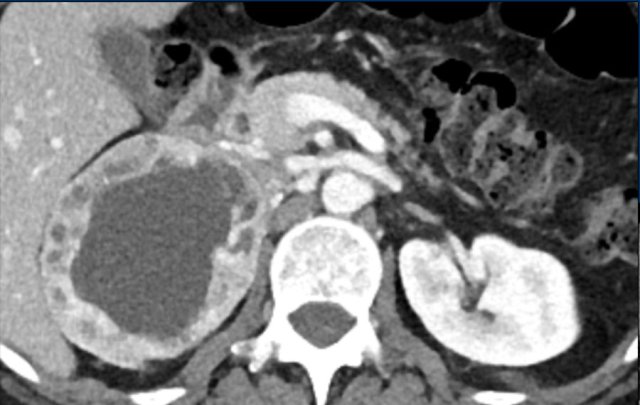

The image shows a 67 mm heterogeneously enhancing relatively well defined lesion.

This proved to be an adrenocortical carcinoma, after resection.